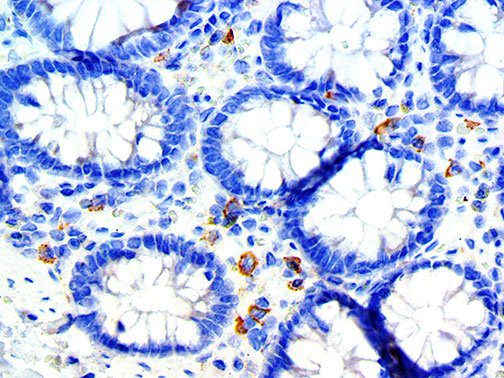

This activation induces inflammatory monocytes to highly express IL-6, starting a localized and then systemic cascade effect that results in hyperproduction of IL-6, which accelerates the inflammatory process. Because IL-6 also increases vascular permeability, excessive levels cause blood vessels to become very leaky. This, along with clotting factors released from vascular endothelial cells, stimulates the coagulation cascade, resulting in microthrombosis (tiny clots), which leads to ischemia and tissue death of the kidney, intestines, heart, liver, brain and extremities.